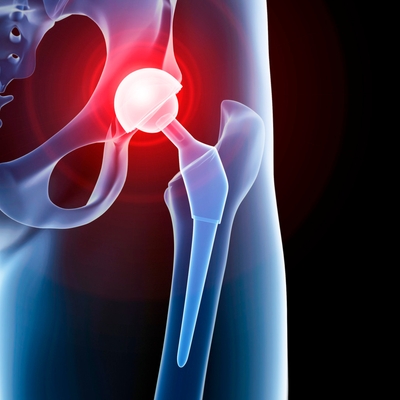

Click on an image below to view more info.